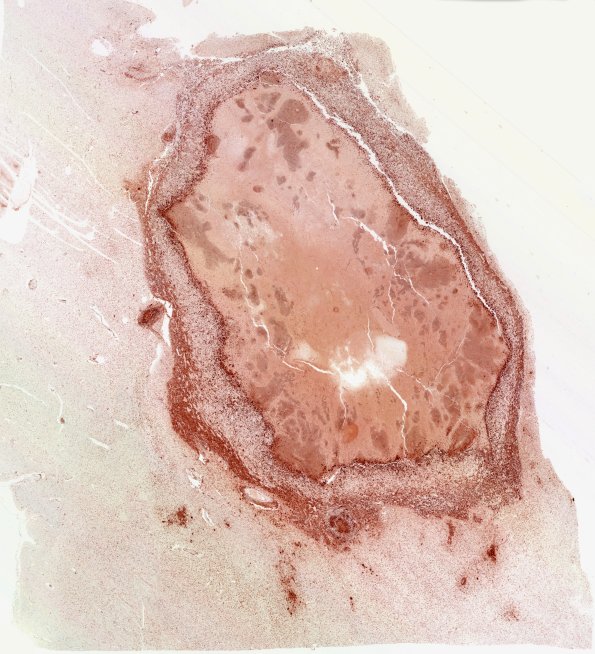

Washington University Experience | INFECTION | Fungus | Mucormycosis - Zygomycosis | 12F Abscess (Case 12) N4 CD68 WM

12F,G The macrophages surrounding necrotic material stain prominently for CD68 (12F) and the histiocytic lineage marker CD163 (12G)